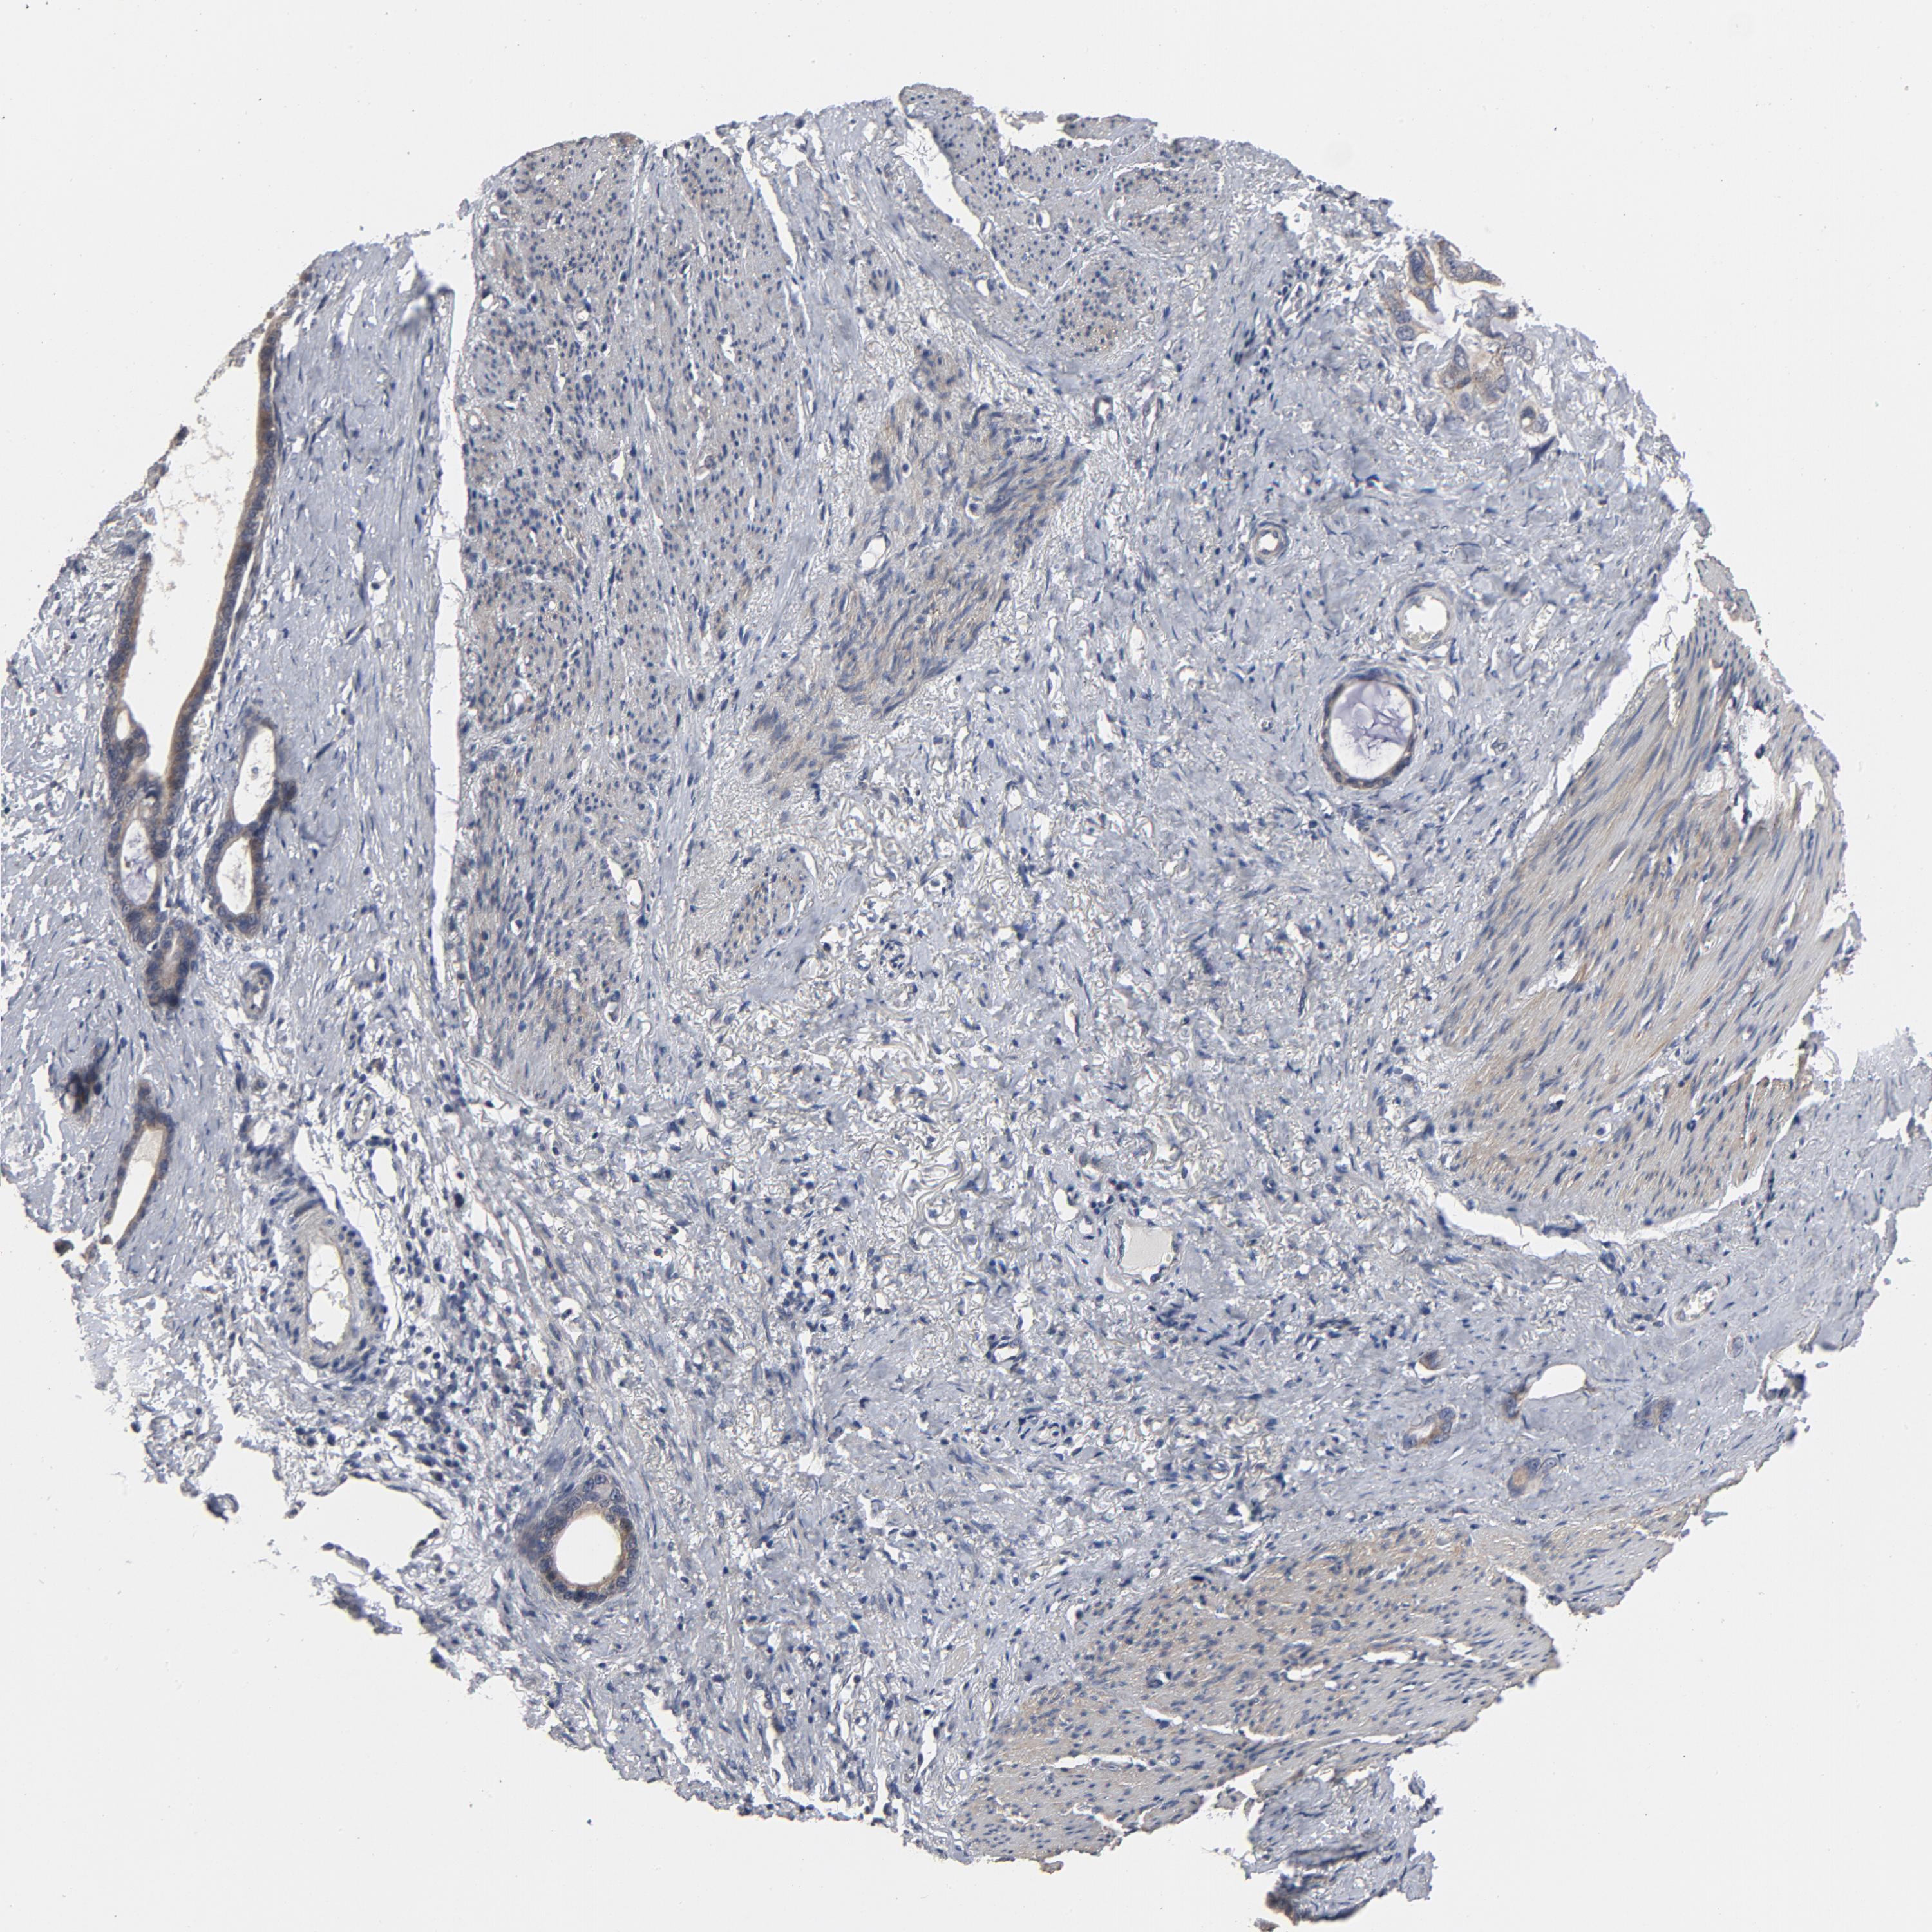

STOMACH CANCER - Protein expressioni

A mouse-over function shows sample information and annotation data. Click on an image to view it in a full screen mode. Samples can be filtered based on level of antibody staining by selecting one or several of the following categories: high, medium, low and not detected. The assay and annotation is described here.

Note that samples used for immunohistochemistry by the Human Protein Atlas do not correspond to samples in the TCGA dataset.

Antibody stainingi

Antibody staining in the annotated cell types in the current human tissue is reported as not detected, low, medium, or high, based on conventional immunohistochemistry profiling in selected tissues. This score is based on the combination of the staining intensity and fraction of stained cells.

Each image is clickable and will lead to virtual microscopy that enables deeper exploration of all samples and also displays staining intensity scores, fraction scores and subcellular localization as well as patient and tissue information for each sample.

Antibody HPA048630

Antibody HPA061142

Antibody CAB004026

Staining

High

Medium

Low

Not detected

Intensity

Strong

Moderate

Weak

Negative

Quantity

>75%

75%-25%

<25%

None

Location

Nuclear

Cytoplasmic/membranous

Cytoplasmic/membranous,nuclear

Adenocarcinoma, NOS

Adenocarcinoma, High grade